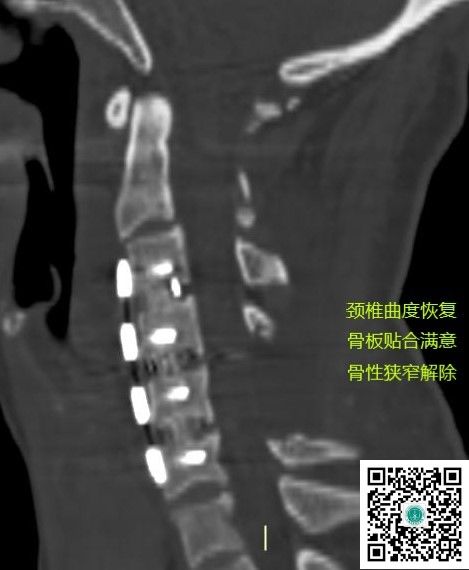

同期行前路内固定,矫正脊柱畸形。

术后CT见颈椎曲度和椎体间高度恢复满意。